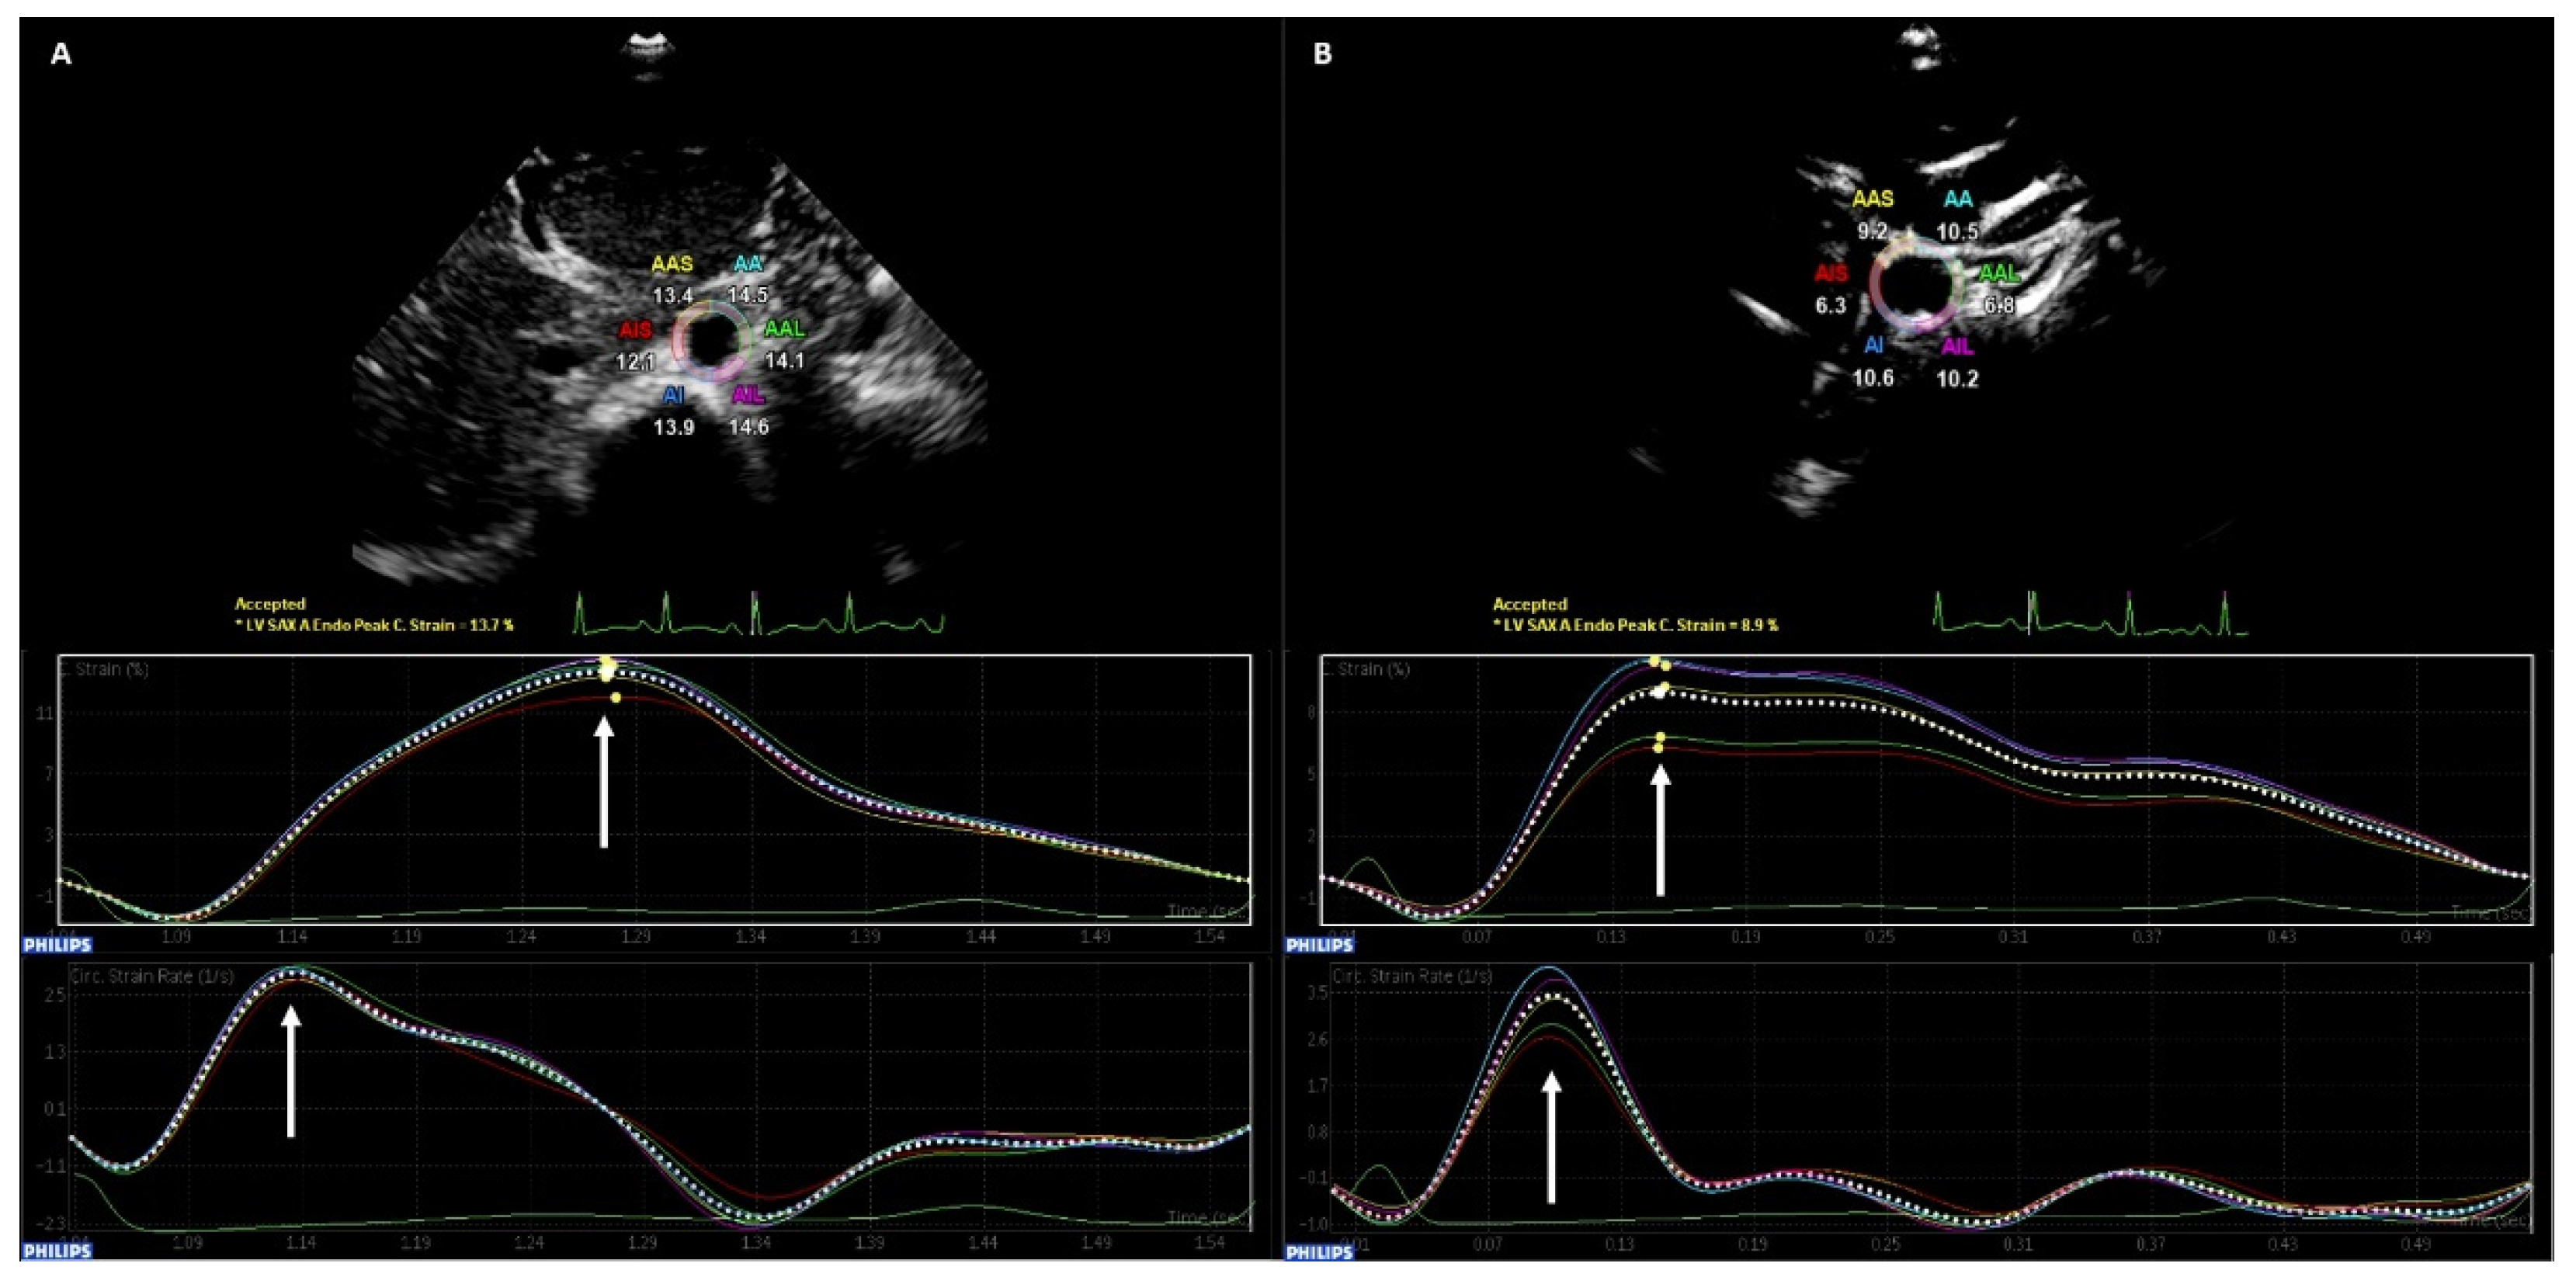

2.6.2. Peak Circumferential Strain, Peak Strain Rate and Arterial Distensibility of the Abdominal Aorta and the Common Carotid Arteries

| rCCA CS (%) 4 | 13.71 ± 3.41 | 14.60 ± 4.68 | 0.18 |

| rCCA SR (1/s) 4 | 3.82 (3.38–4.50) | 4.10 (3.23–4.93) | 0.13 |

| rCCA Dis (mmHg−1 × 10−3) 4 | 580 ± 177 | 628 ± 222 | 0.16 |